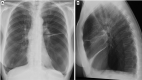

Fig. 3

On chest X-ray of the elderly, a common finding is the elevation of the left hemidiaphragm related to cardiothoracic surgery (A); on the contrary a lowering of the left hemidiaphragm due to increasing heart volume can be frequently seen as well (B). On sagittal MPR reconstruction, typings of the diaphragm caused by chronic obstructive pulmonary disease should not be misinterpreted as pathological findings (C)